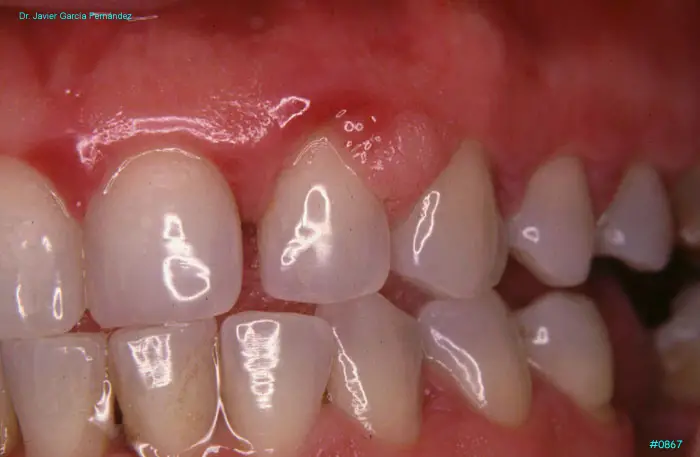

Atlas of Surgical Techniques in Periodontics. Chapter III. Atlas de Técnicas Quirúrgicas en Periodoncia